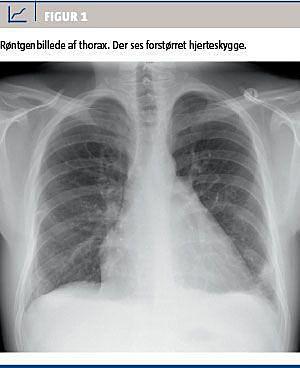

På 11.-dagen fik patienten feber og dyspnø. Blodtrykket var normalt. B-leukocytniveauet var 14,9 × 109/l, og CRP var 266 mg/l. Elektrokardiografi viste sinustakykardi. Patienten var på daværende tidspunkt i behandling med cefuroxim 4,5 g dagligt for pneumoni. Røntgen af thorax viste bilaterale infiltrater og forstørret hjerteskygge Figur 1. En efterfølgende ekkokardiografi viste perikardieekssudat med komprimeret højre ventrikel.

I tilfælde med meningokoksygdom og udvikling af hæmodynamiske problemer og eller kardiomegali set på røntgenoptagelser af på thorax, skal ekkokardiografi altid overvejes, idet problemet kan være hæmodynamisk betydende perikardieeffusion. Behandlingen afhænger herefter af, om der er tale om en bakteriologisk eller immunmedieret perikarditis.